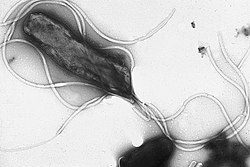

Helicobacter pylori es un bacilo gramnegativo helicoidal caracterizado por proliferar en la mucosa gástrica humana. La denominación del género Helicobacter hace referencia a su morfología en espiral, en tanto que la designación "pylori" alude al origen anatómico de las células por las que ésta tiene afinidad.[1]

Estructura de la bacteria

H. pylori es una bacteria gramnegativa de forma espiral, o espirilo,[14] de alrededor de 3 µm (micrómetros) de largo y con un diámetro aproximado de unos 0,5 µm. Tiene unos 4-6 flagelos. Es microaerófila, es decir, requiere oxígeno pero a más bajas concentraciones de las encontradas en la atmósfera. Usa hidrógeno y metanogénesis como fuente de energía. Además es oxidasa y catalasa positiva.

Con su flagelo y su forma espiral, la bacteria «taladra» literalmente la capa de mucus del estómago, y después puede quedarse suspendida en la mucosa gástrica o adherirse a células epiteliales ya que produce adhesinas, (que son proteínas fijantes). H. pylori produce una enzima llamada «ureasa» que transforma la urea en amoniaco y en dióxido de carbono mediante la reacción: CO(NH2)2 + H2O → 2NH3 + CO2, y es el amoniaco el que va a neutralizar parcialmente la acidez gástrica (que sirve para disolver los alimentos y matar la mayor parte de bacterias digeridas). Lamentablemente el amoniaco es tóxico y va a maltratar la superficie de las células epiteliales y provocar el proceso de formación de las úlceras.